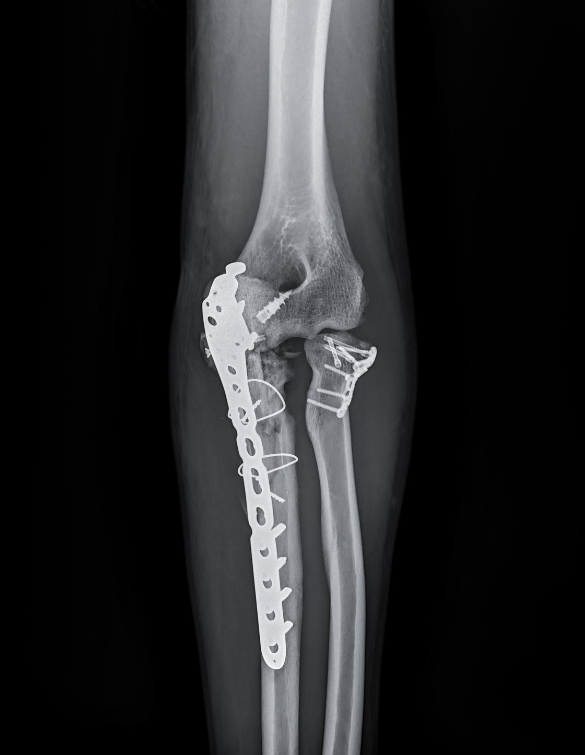

Surgical procedures are performed using modern fixation systems (suture anchors, buttons, or screws) that ensure durable healing. Our minimally invasive techniques minimize tissue disruption, reduce recovery time, and enhance cosmetic results. Whether the injury involves the biceps, triceps, or extensor/flexor tendons, our goal is to restore full strength and motion safely and effectively.